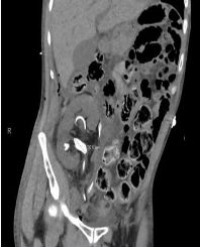

Transplant Renal Artery Stenosis Following Ex vivo Renal Artery Endarterectomy: Report on Two Cases

Introduction: Transplant renal artery stenosis (TRAS) is the most common vascular complication following kidney transplantation. Deceased donor kidneys exhibiting severe atherosclerosis involving the renal artery, if untreated, represent one cause of TRAS.

Methods: We report herein two cases of TRAS that occurred following back bench ex vivo eversion endarterectomy (EE) prior to deceased donor kidney transplantation (DDKT).

Results: Both patients presented in the first year following DDKT with worsening hypertension and one patient experienced acute kidney injury. Duplex ultrasonography was suspicious for markedly elevated renal artery velocities in the proximal to mid-renal artery segment with evidence for distal turbulence. Subsequent arteriography through an ipsilateral femoral approach confirmed severe TRAS that was successfully treated with balloon angioplasty and stenting. Both patients experienced improvements in blood pressure control, and one patient had resolution of acute kidney injury.

Conclusion: Ex vivo EE may be performed successfully as a rescue procedure to prevent nonuse of donor kidneys with severe intrinsic atherosclerosis. However, these patients may still be at risk for developing TRAS, possibly from a localized dissection occurring secondary to an intimal flap.